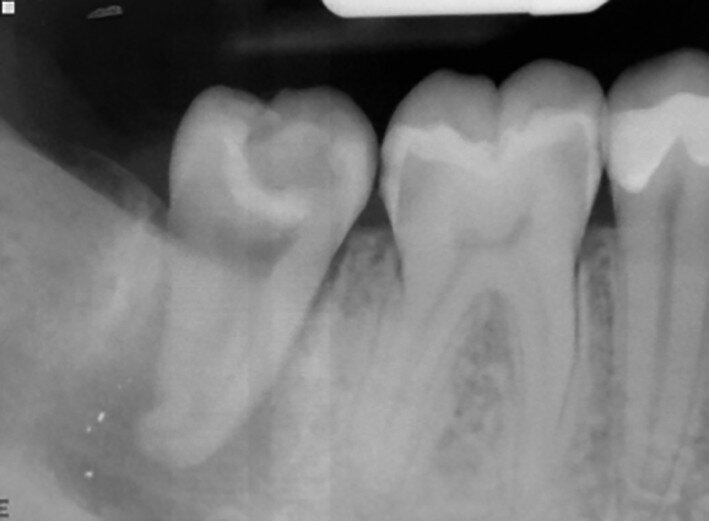

Fig. 19a: Radiographs: Pre-op periapical.

A 16-year-old female patient required extraction of a maxillary molar. Tooth #18 was transplanted to site #16. Root development was still continuing after two years (Figs. 19a–d).